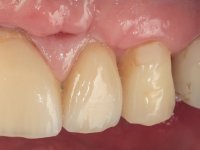

6 meses após a colocação da ponte, o paciente sofre um novo traumatismo comprometendo a viabilidade dos dentes 1.2 e 1.1. Foi realizada uma prótese removível acrílica para reabilitar provisoriamente o paciente enquanto foram extraídos os dentes 1.2 e 1.1 e foi colocado o implante no local do dente 1.1. Passados 3 meses foi realizada uma impressão ao implante colocado no 1.1 e simultaneamente foi feito um arrasto da ponte dos dentes 2.1 e 2.2. Para esse efeito no implante 2.1 foi utilizado um parafuso de uma peça de transferência. Dessa forma conseguiu-se impressionar corretamente a arquitetura gengival do sector antero-superior. O objetivo era simultaneamente impressionar corretamente esta zona e aproveitar a estrutura metálica desta ponte para confecionar a nova ponte de 4 elementos. Foi colocado um parafuso de cicatrização no implante 2.1 e foram acrescentados os dentes 2.1 e 2.2 na prótese removível. Com perícia laboratorial foi criada uma nova infraestrutura metálica de 4 elementos assente nos implantes 1.1 e 2.1 e com os elementos pônticos suspensos 1.2 e 2.2. No implante 2.1 manteve-se a conexão interna ao implante no implante 1.1 optou-se por uma peça intermédia facilitando a inserção da infraestrutura. A nova infraestrutura foi verificada em boca. Como pode ter havido alguma alteração da arquitetura gengival com a remoção da ponte e colocação do parafuso de cicatrização no 2.1, foi feita uma chave de silicone para permitir uma impressão de arrasto da infraestrutura metálica. Uma nova gengiva artificial foi realizada no modelo de trabalho de acordo com esta impressão de arrasto. Foi colocada cerâmica de tonalidade coronária e gengival. A peça protética foi aparafusada lentamente em boca para permitir uma adaptação dos tecidos moles. Após o correto assentamento e verificação imagiológica a ponte foi definitivamente apertada em boca e os orifícios de acesso obturados. Independentemente dos infortúnios que o paciente teve, pude ter a satisfação de o ver contente com esta reabilitação.